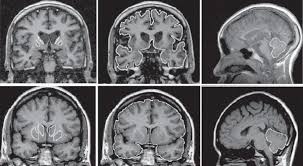

Hoy les vamos a informar sobre las siguientes enfermedades discapacitantes que se dan entre nuestro colectivo de la dependencia. Con ello pretendemos informar únicamente a todas aquellas personas que no están debidamente informadas de nuestras patologías y por esa causa, la mayoría de las ocasiones, opinan digamos así que "por boca de ganso" ya que todas ellas ofrecen ciertas dificultades que debieran tomarse con mucha más consideración.